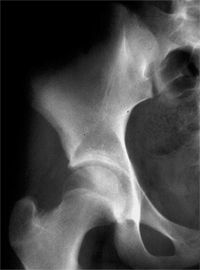

Figure 24.23 Radiographic subluxation and dysplasia. A:

A 36-year-old woman with bilateral anatomically abnormal (dysplastic) hips. The left hip is radiographically subluxated, with the Shenton line disrupted, and the right hip is radiographically dysplastic, with the Shenton line intact. B: Seven years later, note the marked loss of joint space in the secondary acetabulum of the left hip and very early disruption of the Shenton line on the right. The right hip is asymptomatic, and the left hip is about to undergo total hip arthroplasty. |